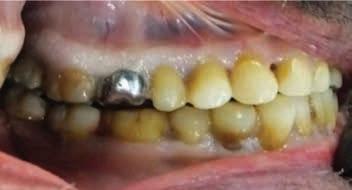

Scene Description: An unidentified Hispanic male was found by a worker mowing grass near the back parking lot of a Domino’s restaurant in Ft. Worth, Texas, on 6-28-2022. The decedent was lying unresponsive in a supine position on the pavement between a dumpster and a cargo shipping container when Ft. Worth police arrived at the scene. Video surveillance obtained from the restaurant caught the decedent moving around on camera near the dumpster at 1800 hours on 6-28-2022. The decedent was clad in pants and a belt. No signs of medical intervention were observed, and brown emesis was present around the decedent’s mouth. No foul play was suspected.

Dental Evidence Recovered: Maxilla and Mandible

Right Left

Right Lateral View

Left Lateral View

Periapical Tooth #3 (Root Canal Treatment)

Periapical Tooth #14 (Root Canal Treatment)

#3 #14